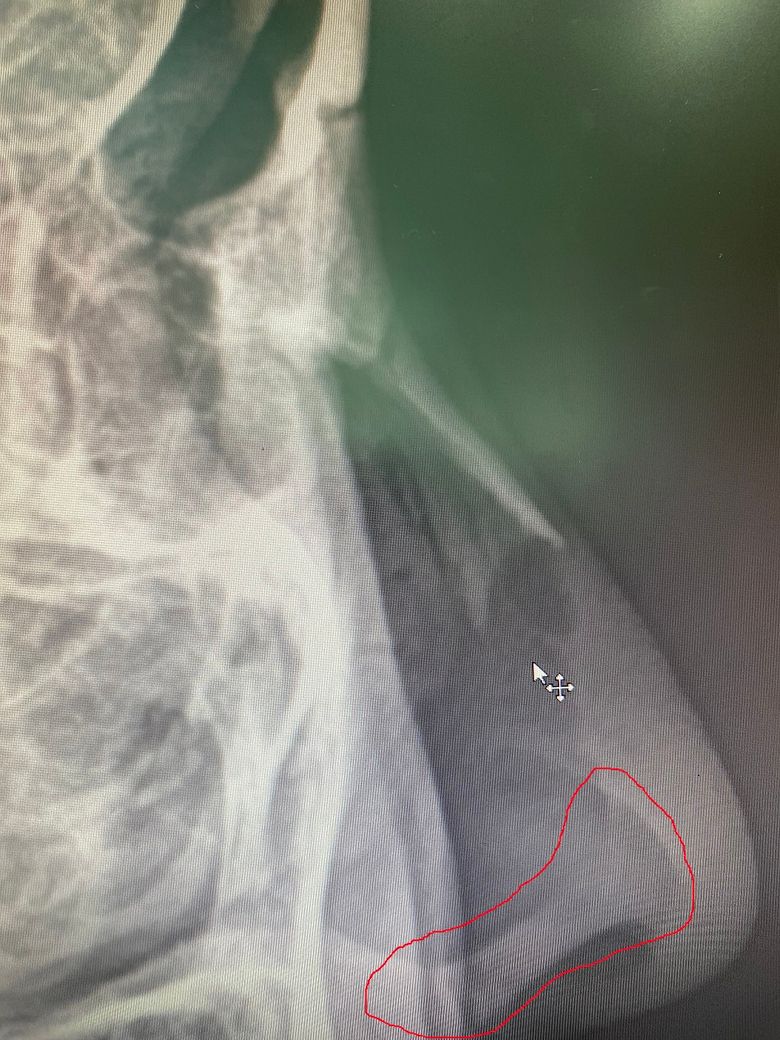

코 엑스레이 사진을 살펴보니 콧구멍 주변에 뭔가가 보이는데요.

사진에서 제가 빨간색으로 표시한 부분이요. 콧구멍 바로 위에 하얗게 보이는 부분요.

이게 뭔가요? 갑자기 궁금증이 생겨서 질문드립니다.

코중격 연골인 것으로 판단됩니다. /////////////////////////